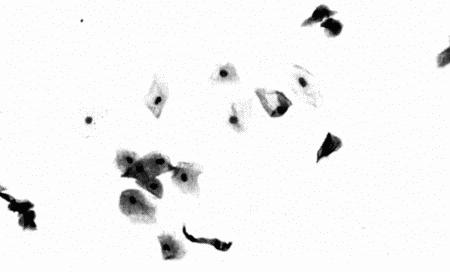

Фиг. 4.2.

Та же самая сука 7 дней спустя. Характер выделений соответствует анэструсу, концентрация прогестерона на базальном уровне. В мазке преобладают парабазальные и промежуточные клетки, выделения содержат значительное количество слизи. Через три недели характерные для проэструса кровянистые выделения возобновились, после чего имела место нормальная овуляция (см. Приложение)